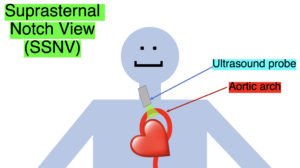

Point-of-care cardiac echocardiogram demonstrated a dilated ascending aorta (illustrated in red) measuring approximately 4 cm in the parasternal long axis (PLAX). A dilated aortic arch (illustrated in green) also measuring approximately 4 cm was appreciated using the suprasternal notch view (SSNV). A follow-up computed tomography angiogram (CTA) was performed, validating bedside ultrasound measurements.

The diagnostic criteria for dilated thoracic aneurysm is based on multiple factors including age, sex, and body size.2 An aortic root diameter of ³ 4.0 cm constitutes an ascending aortic dilation.3,4 Point-of-care cardiac and SSNV ultrasound of the thoracic aorta has been validated as an accurate study when performed by emergency physicians to identify thoracic aortic aneurysms (sensitivity of 71.4%, specificity of 100% when compared to gold standard of CTA). 5 This case is an example of the utility of rapid bedside diagnostic ultrasound, specifically the SSNV, in assessment of thoracic aneurysms.

Point-of-care cardiac echocardiography demonstrated a dilated ascending aorta. Finding a new thoracic aortic aneurysm in the setting of chest pain and hypertension is a “can’t miss” diagnosis due to the potential for rapid expansion leading to dissection and/or rupture.6 Point-of-care ultrasound utilizing the SSNV is a tool that can be used early in the evaluation of the patient that can help make quick determination of diagnostic plan and expedite initiating treatment in the emergency department.